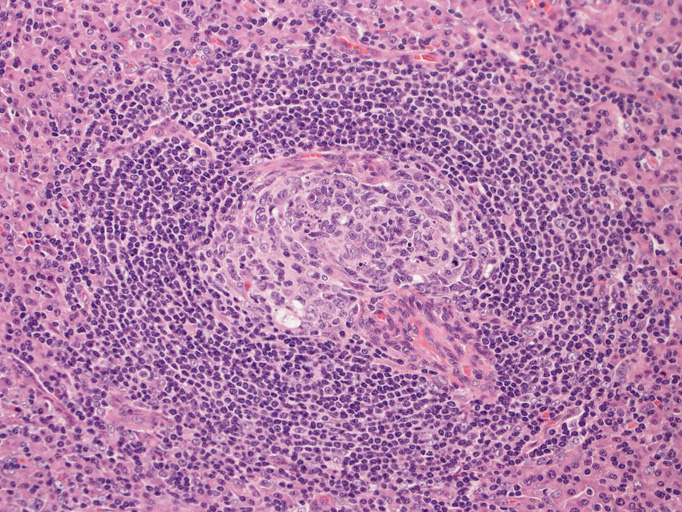

硝子血管型 hyaline vascular type: 臨床症状に関係なく3つの病理組織所見で診断が決まる。*1

1. 萎縮した胚中心をもつ異常な血管増生を示すリンパ濾胞(Lolli-pop follicles. Lolli-popはキャンディ-の名前のようです)

2. 濾胞間リンパ組織の線維化, 血管増生

- 濾胞は小型で周囲を広いmantle zoneで囲まれている。同心円状のよく発達したmantle zoneは「onion skin」と呼ばれる。濾胞は濾胞樹状細胞と進入血管の内皮から構成されている。ときに大型奇異,「異形」細胞が見られるが異常な濾胞樹状細胞と考えられる。-> Dr. Castlemanが「Hodgkin diseaseとの鑑別が必要」といった症例がこのような例に相当すると考えられる(Dr.小島)

「広いmantle zoneの取り巻いたリンパ球の少ないFDCのめだつ小さな濾胞, 硝子化することもある, 濾胞間は細血管でいっぱい」がkey word